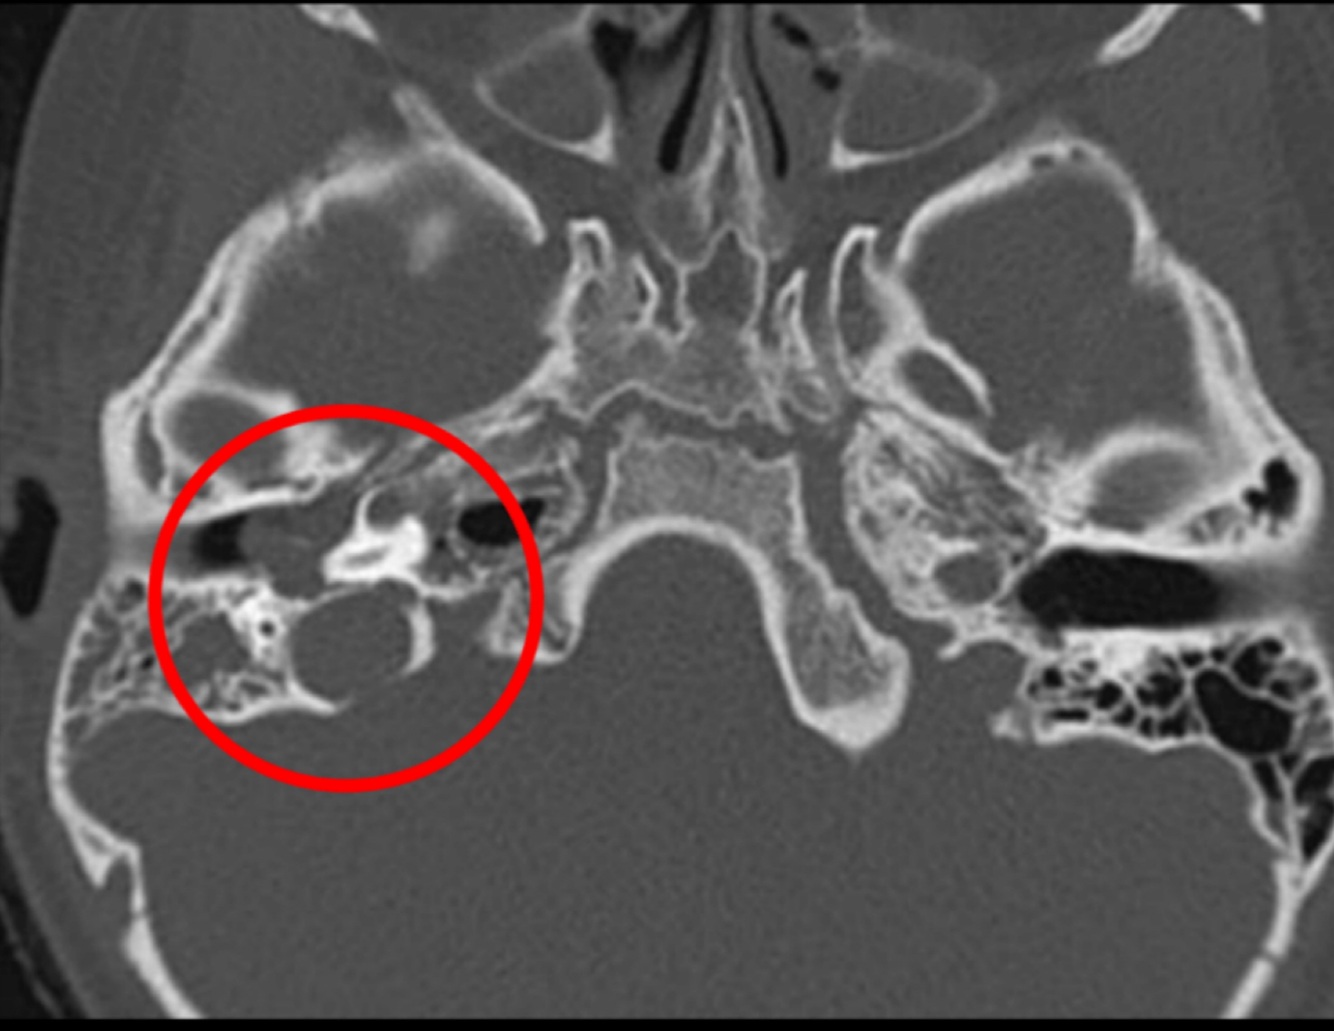

¿Qué es el colesteatoma?

• Neoplasia benigna de comportamiento maligno

• Tejido epidérmico que crece e el interior del conducto auditico

• Complicación de ostomastoiditis

¿Por qué colesteatoma tiene comportamiento maligno?

Destruye hueso y cadena osicular

Hallazgos en imagen:

RM o TC

• Otitis y mastoiditis

• Masa que destruye hueso

A (afectado): se pierden huesecillos

Estudio de imagen dx para colesteatoma:

DWI

Hiperintensa en T2